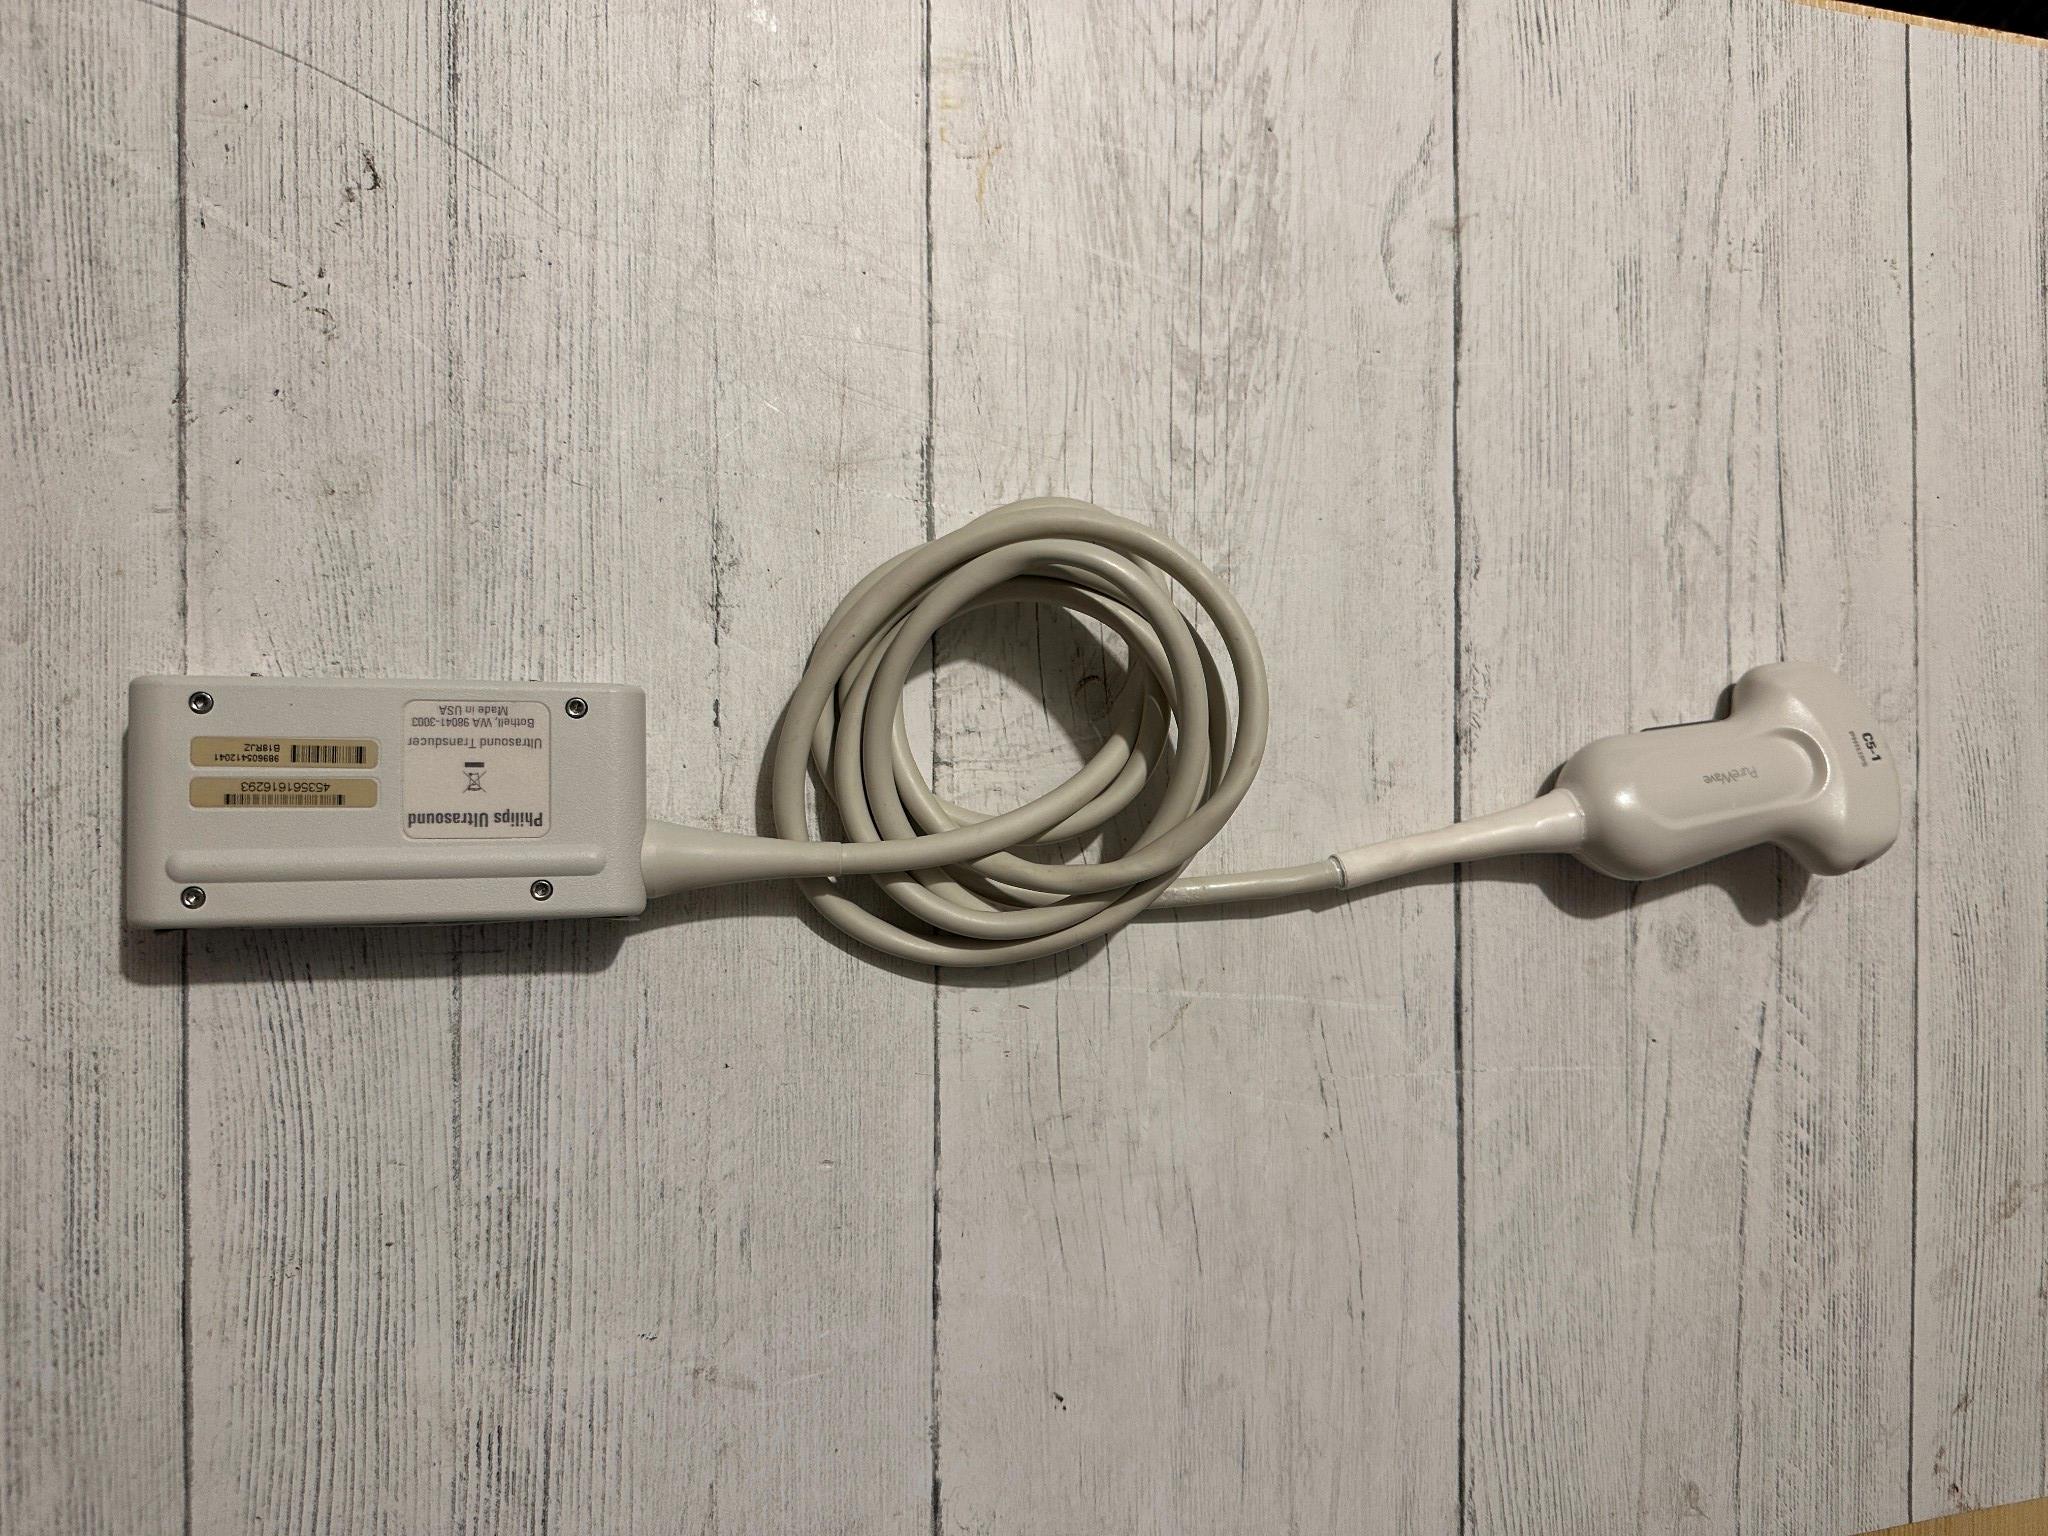

DIAGNOSTIC ULTRASOUND MACHINES FOR SALE

GE RSP6-16-RS Ultrasound Volumetric Probe 2011

Sale price$ 6,690.08